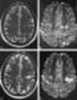

Gyriform cortical/subcortical T2 hypointensity

Acute cortical infarction

Acute subarachnoid hemorrhage

Meningitis

Subacute cortical infarction

Superficial siderosis